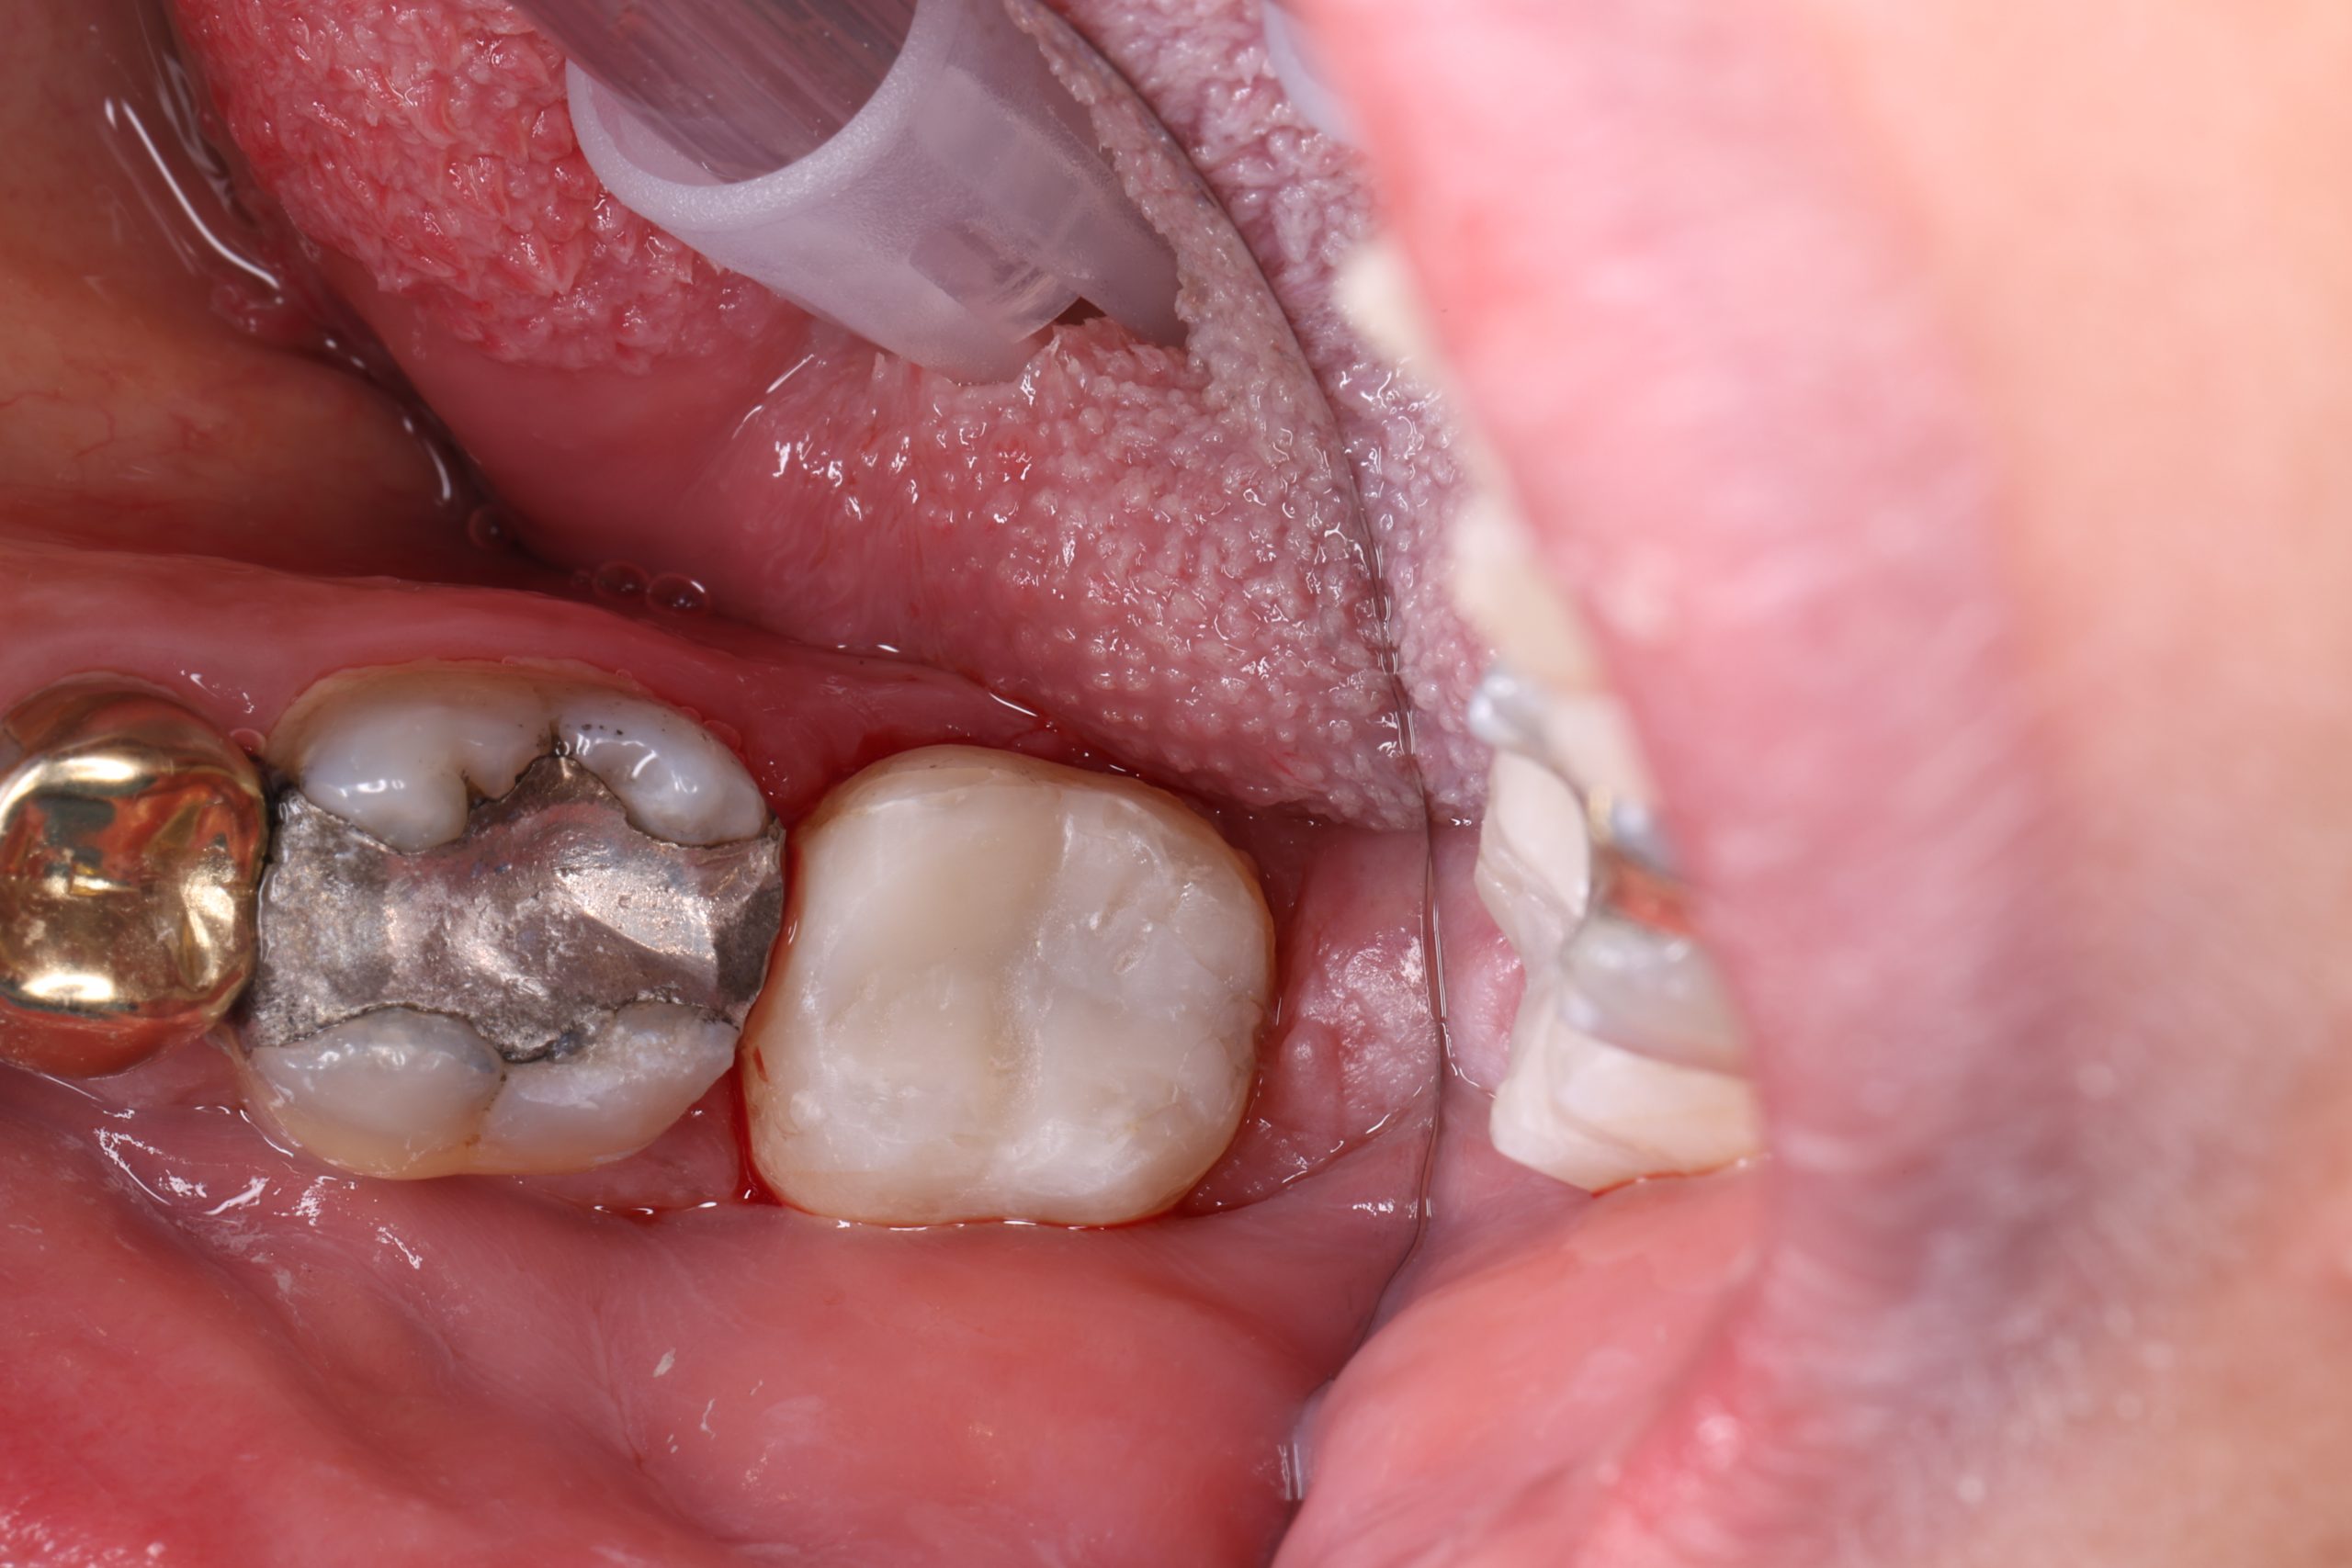

2. Etching and Bonding

A specialised adhesive is applied to create a secure link between your tooth and the composite. Strong bonding prevents leakage, improves longevity, and protects the tooth.

4. Curing with Light

Each layer is hardened with a curing light for predictable strength and stability.